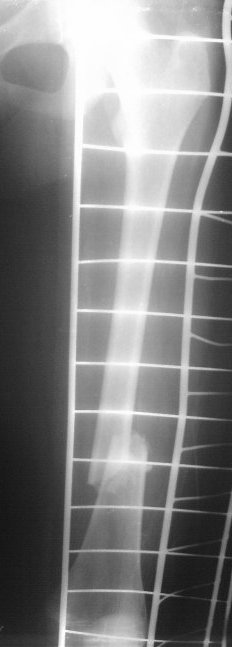

На сегодняшний день вот такая картина: девочка, 13 лет, 3 недели на скелетном вытяжении по поводу оскольчатого перелома нижней трети левого бедра.

Сейчас инфекцию "победили", отек бедра за последние дни значительно спал, но имеется укорочение 2 см, отломки уже "прихватились",патологической подвижности нет.

Добрый вечер!Такое впечатление,что система постоянного скелетного вытяжения не работала,какой был груз по оси?Стояние отломков неудовлетворительное,дополнительно обследовать и принимать решение оперативного лечения,попробуйте добавить груз по оси, если растяните, можно и ВО ЧКО по Илизарову.И конечно выбор антибиотика.Удачи!

Да, скелетное вытяжение тут как-то не сработало так как хотелось бы. Груз 6 кг (вес 45 кг). Сейчас уже, видимо, расчитывать на вытяжение не приходится, т.к. мозоль начала формироваться и подвижность исчезла.

Как-то вот совсем бы не хотелось открываться-то. Осколков, там похоже не один, а два как минимум (не совсем хороши снимки). Боюсь, что накостный остеосинтез, даже перкутанный, привяжет пациенку к отделению еще больше. После гнойной лихорадки, мождет и "полыхнуть", так что "мама не горюй". Риск, думаю, сохраняется.

Больше склоняюсь к закрытому остеосинтезу TEN либо гвоздем, и все в одну сессию. Интересует все-же, мнение по-поводу седалищного нерва. Острое восстановление длины бедра после иммобилизации. У взрослых - неврологии не встречали, а вот у детей ...

TEN v13 let rabotaet ne ochen:mnogo malunions.Ya by postavil regid IMN.Sudya po snimkam growth plates closed.Luchshe konechno postavit trochanteric nail-net opasnosti AVN.Drugaya opzya posle rastyaghenya(oh namuchaetes!),postavit bridging long plate:prosto ikrasivo.

Переделаем снимки. Мне кажется, что зона роста еще работает, хотя четко сказать нельзя. Да, трохантерный гвоздь 8 мм - тут наверное, самое оптимальное решение. Если возьмемся работать TEN, то возьмем стержни по 3 мм.ИМ канал узкий, в истмусе где-то 8-9 мм. В сумме объем занимаемый TEN заполнит ИМ канал больше чем на 60%, плюс "трехточечная" фиксация, может и сработает и не допустит malunions в дальнейшем.

Это снимки при поступлении, похоже.

Я бы сделал свежие. Пока предполагаю, что раз срок большой, возраст маленький, то, вероятно, лучше в два этапа - - аппаратом растянуть за неделю, а потом заштифтовать. Раз старше 12 лет, то согласен с Марком, не TENами, а нетолстым ригидным стержнем с латерализованным проксимальным отделом. Зона роста если и пострадает, то всего одна, и за оставшейся период роста не успеет сформироваться разница длин.